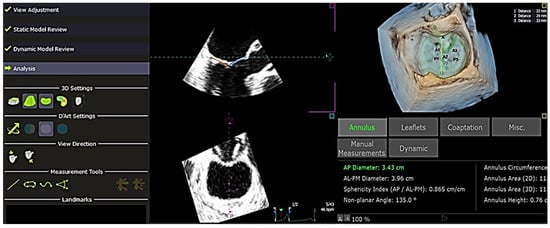

2.2. QLAB 13 Software Analysis

The software used to analyze the 4D echocardiography data was QLAB 13, an experimental, unreleased software developed by PHILIPS and TomTec, which was approved by the FDA on 18 June 2019. A set of Q-apps analysis tools equipped in the software could be selected for the quantitative analysis of echocardiographic data. These tools included 4D Mitral Valve Assessment (MVA), Mitral Valve Navigation (MVN), General Imaging 3DQ (GI3DQ), etc. The MVA feature was used to perform echo analysis, allowing the extraction of essential variables for the study. The positions of the mitral valve annulus and leaflets were automatically generated by the software, outlined using “points” and “lines” superimposed on the approximated margins of the mitral valve, as shown in Figure 1. These “points” and “lines” could be adjusted manually to gain a more accurate approximation of the actual position of the mitral valve using the next three stages of review, namely, view adjustment, static model (Figure 2), and dynamic model (Figure 3) reviews.

Figure 1. Alignment of “points” and “lines” to mitral valve—view of the mitral valve in the QLAB 13R software. The line in green marks the position of the left atrium and the left ventricle. The points demarcate the position of the mitral annulus, aortic annulus, anterior point, and coaptation/valve closure. There is a total of 7 points and 2 lines under “View Adjustment”, which need to be adjusted according to the reference provided at the left side. During the adjustment, it is allowed to pause at a single frame, which is helpful for placing the points and lines in their respective positions more accurately. After finishing the “View Adjustment”, it proceeds to “Static Model Review”. A = anterior point, AA = aortic annulus, CL = coaptation/valve closure, MA = mitral annulus, LA = left atrium, LV = left ventricle, LAX = long axis, SAX = short axis.